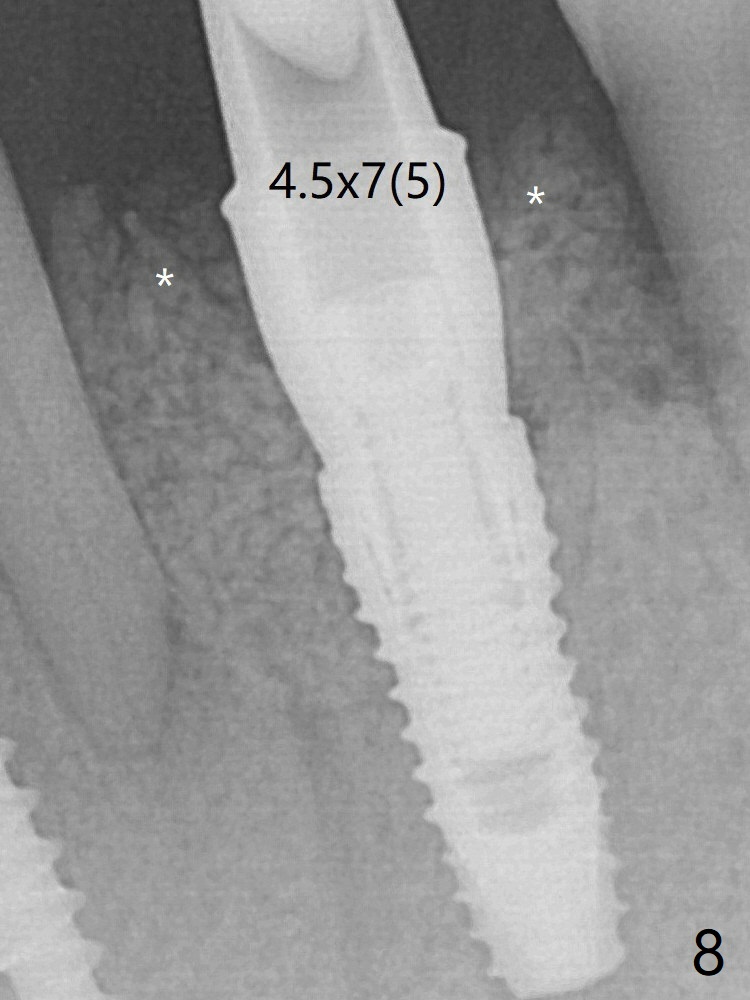

A 3.8x10 mm dummy implant is placed tentatively with an apical space (Fig.4 (the distal root surface of the lateral incisor is denuded (<)). When a same dimension definitive implant is placed with 40 Ncm, it is 2 mm below the lingual gingival margin, whereas 6-7 mm below the buccal one (Fig.5). Vanilla graft is placed before placement of a 5.5x4(5) mm abutment (Fig.6). The root surface of the lateral incisor is covered by the bone graft. Later the abutment is changed to a longer and smaller one (Fig.8) with more of the allograft (*). The short implant is chosen because it has to be placed deep to prevent periimplantitis, especially lingually, in spite of the fact of the unfavorable crown/implant ratio (Fig.4). The diameter of the implant is small so that there is ample space to pack bone graft both buccally and lingually. The majority of the bone graft seems to be in place 8 months postop (Fig.12).